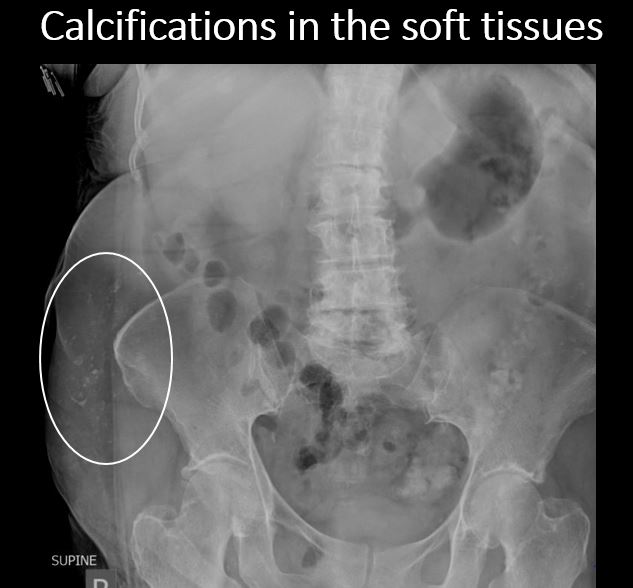

There are dystrophic or additional intra-abdominal soft tissue calcifications. |

No | NA |

There are dystrophic calcifications in the extra-abdominal soft tissues. |